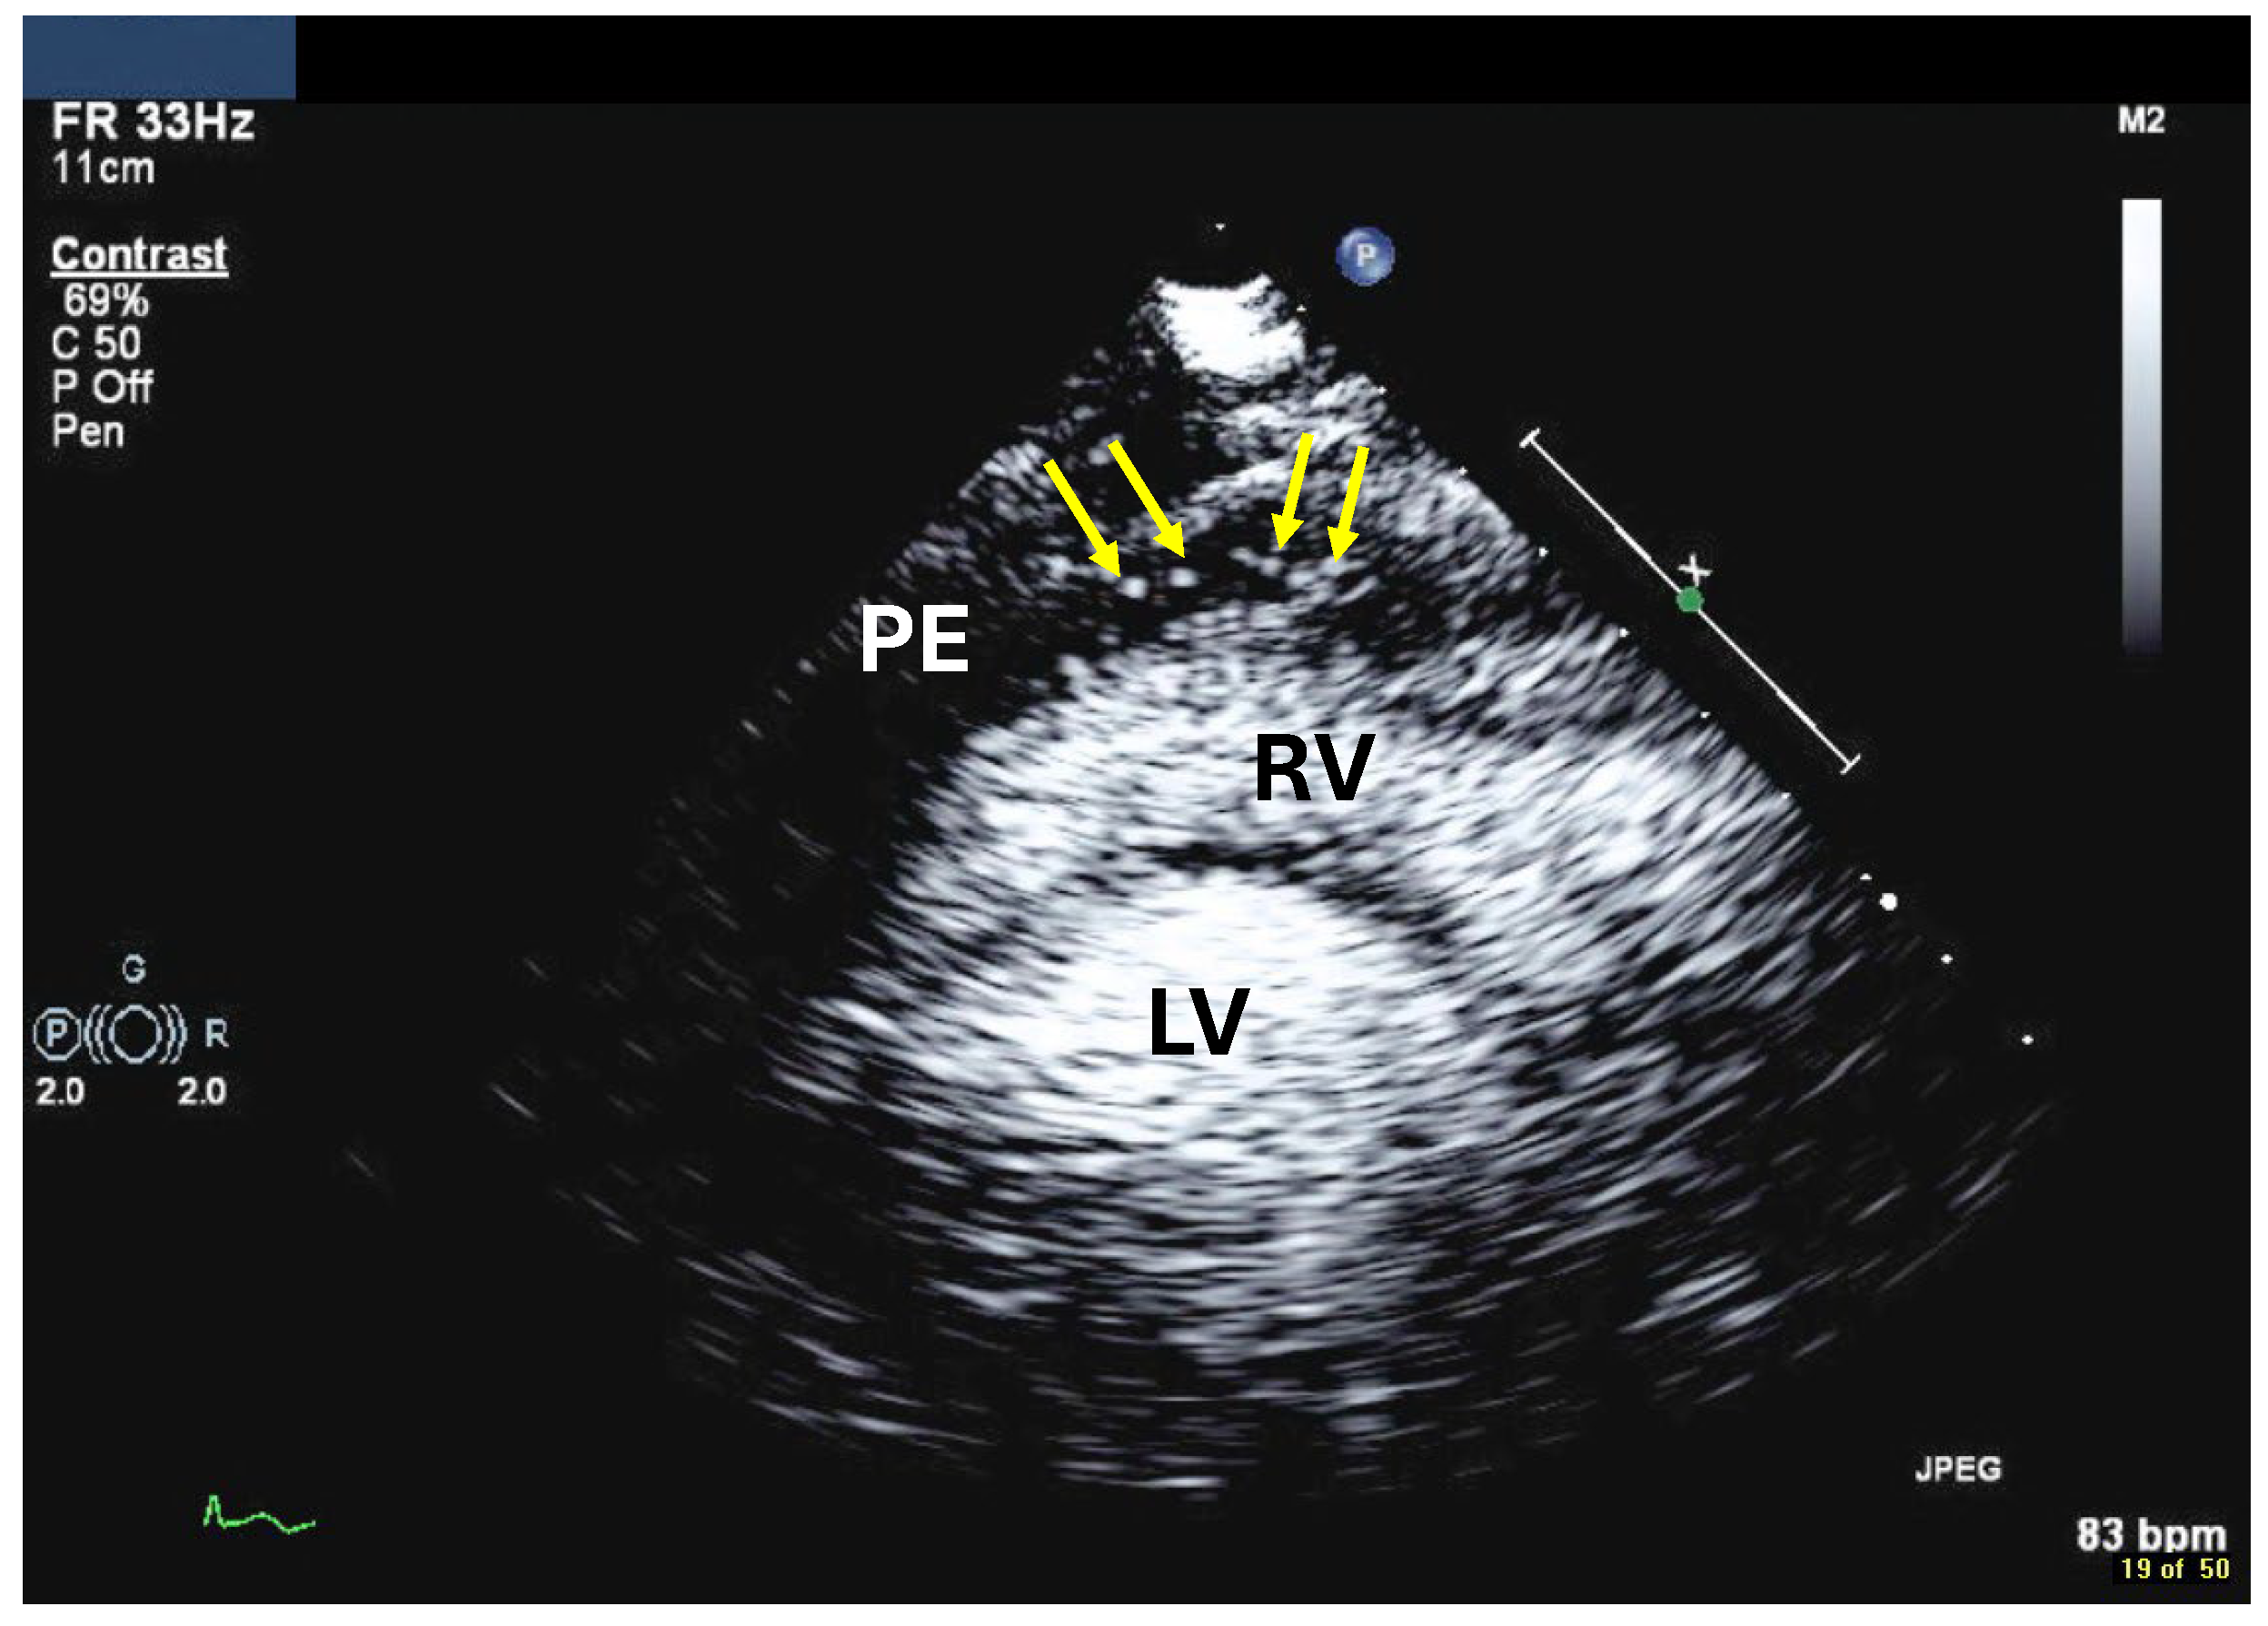

3. Left Ventricular Thrombi and Tumors

3.1. Background and Indications

| Imaging method | Low-MI-contrast-specific imaging and intermediate-MI-contrast-specific imaging |

| Imaging planes | standard apical views additional zoomed views sweeps through the region of the suspected thrombus |

| Sector depth/width | Entire LV + 1/3 LA to assess global/regional LV function, zoomed views of the region with the suspected thrombus |

| Focus | At the depth of the suspected thrombus |

| Gain | Adjust to avoid obscuring the thrombus by intensive opacification of the cavity |

| Contrast application | bolus injections |

| Typical findings | 1. echofree mass 2. present in two different imaging planes 3. lump or laminar shape different from trabeculations’ documented size (two orthogonal diameters in at least one of the views), location, type (laminar vs. lump, single vs. multiple), surface (smooth vs. irregular) and mobility |

| DD tumor vs. thrombus | Opacified (vascularized) masses are suggestive of tumors; the vascularization can be demonstrated with myocardial perfusion imaging. CAVEAT: There are malignant tumors which appear avascular on CEUS. Tumors often are attached to normal myocardium. |

| Alternative imaging | Thrombi: Cardiac MRI when contrast echo is not possible or non-diagnostic, cardiac CT when cardiac MRI is not available Tumors: MRI provides tissue characterization and should be performed unless there is typical myxoma (attached to the interatrial septum) |